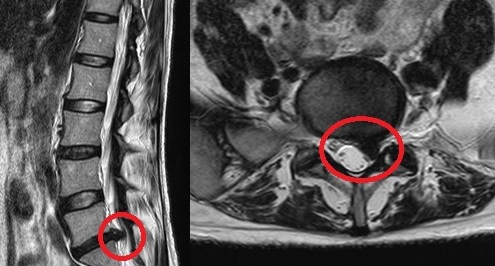

PELD (percutaneous endoscopic lumba discectomy) 내시경 레이저 디스크 수술은 허리 디스크로 인한 허리통증 및 하지 방사통을 완화하는 것을 목적으로 합니다. 허리 중앙에서 옆구리 10cm 정도 떨어진 위치에서 미세관을 디스크 속에 삽입하여 내시경을 이용해 모니터로 확인하면서 디스크에 병적인 수핵만을 제거하고 정상적인 수핵을 보존하는 수술입니다. 보존 요법과 수술 요법 사이에 있는 미세 또는 최소 침습 치료법으로 레이저를 사용하여 신경 압박으로 통증을 유발하는 수핵만을 제거하는 비관혈적 시술로 절개수술이 아니므로 신경, 근육에 손상을 주지 않습니다.